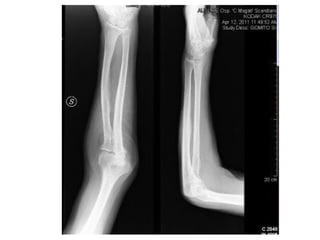

INCIDÊNCIAS COTOVELO

AP

PERFIL